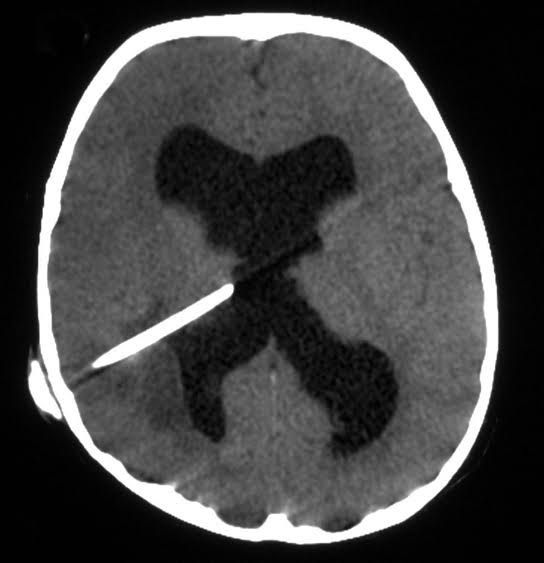

Brain abscess

A brain abscess is a pus-filled swelling in the brain. It usually occurs when bacteria or fungi enter the brain tissue after an infection or severe head injury.